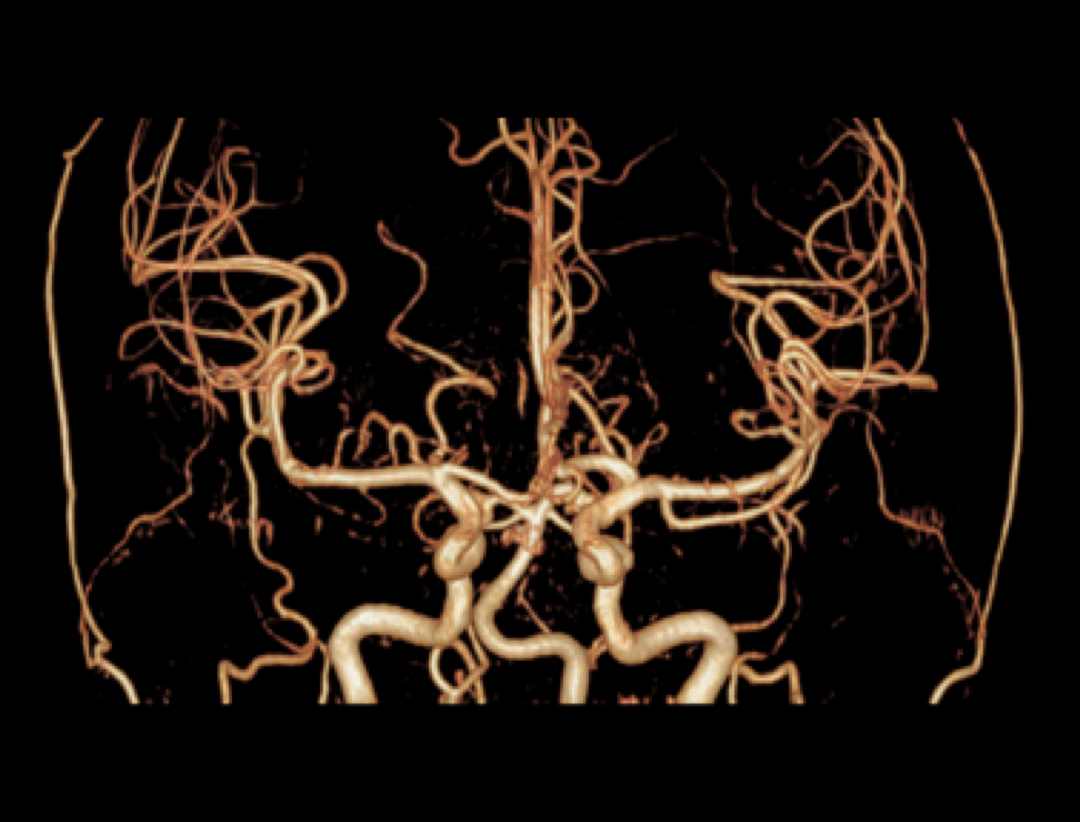

Dzięki opracowanej przez UIH technologii korekty uMR®580 cechuje się doskonałą jednorodnością pola magnetycznego.

Inteligentna technologia kompensacji prądów wirowych zapewnia wysokie parametry gradientów uMR®580.